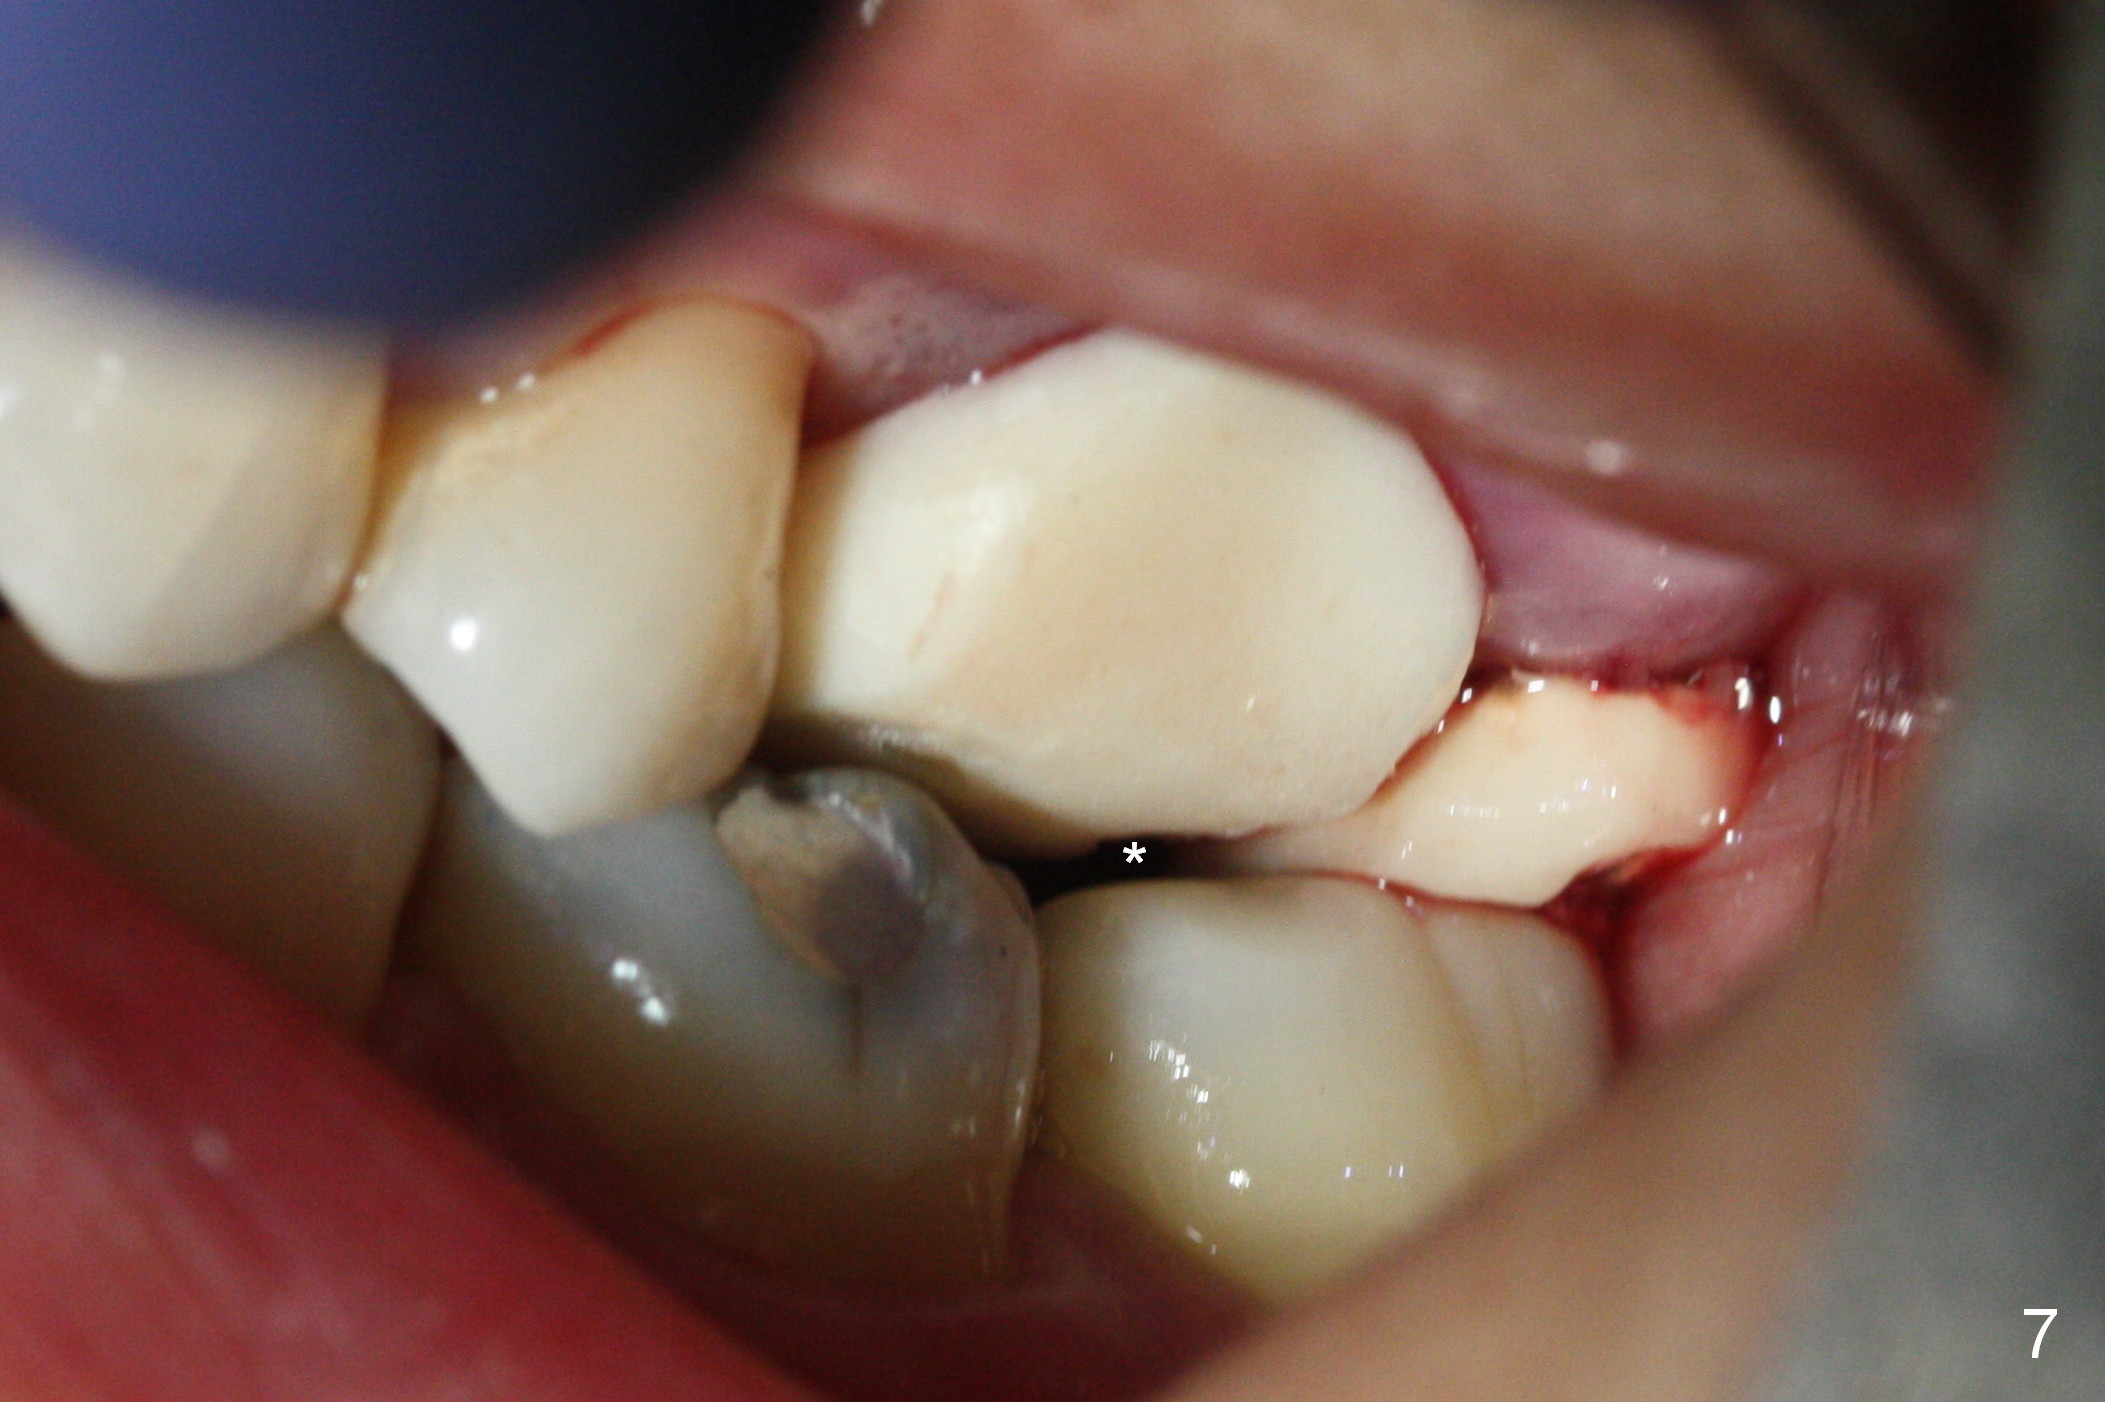

There is abundant subgingival calculus on the surfaces of the extracted tooth at #14 (Fig.1: P: palatal; MB: mesiobuccal), corresponding to the large empty socket (Fig.2 without septal bone, the buccal plate being low). Osteotomy is established palatally with Magic Expander (ME) 3.0 mm for ~ 3 mm deep (Fig.3,4) with minimal stability so that it moves during X-ray taking (Fig.4). Since the bone is dense, Magic drill 4.3 mm is used after application of ME 3.8 and 4.3 mm to complete sinus lift (Fig.5 (panoramic X-ray)). A 5x11 mm implant is placed with ~ 30 Ncm, followed by insertion of 6.5x4(3) mm Hexa abutment, bone graft and collagen membrane (Fig.6). The latter is kept in placed with an immediate provisional with clearance from the opposing dentition (Fig.7 *). Between the 1st and 3rd weeks postop, the buccal gingiva recedes with loss of bone graft (Fig.8 <) and implant thread exposure (Fig.9 * (A: abutment)). After inducing hemorrhage, allograft is placed (Fig.10 >), followed by collagen dressing (Fig.11 >). The wound closes by adding new acrylic (Fig.12 *). Thirteen days later, food is trapped in the buccal gap (Fig.13 ^). It appears that the provisional does not help wound healing. The provisional and abutment are removed; incorporating bone graft (Fig.14 *) and the implant are exposed. After placing collagen plug against the bone graft and implant, the wound is closed by periodontal dressing.